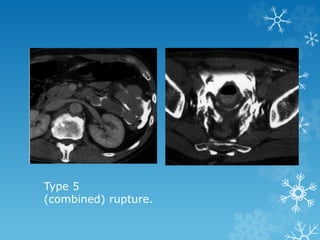

TYPES

4. Extraperitoneal rupture

5. Combined bladder injury

Type 5

(combined) rupture.